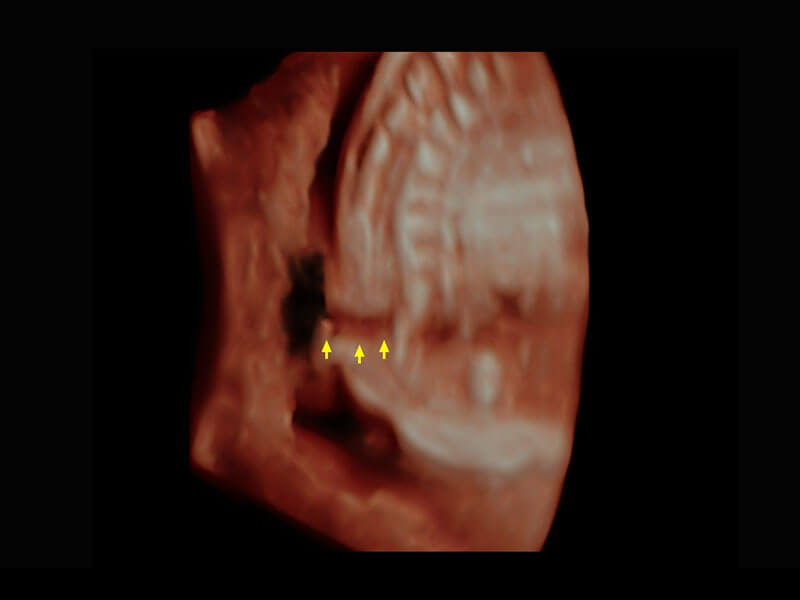

生殖健康

P60优异的图像质量搭载专科探头,在妇科基础疾病的诊断、卵泡生长的监测、输卵管通畅情况的判别等方面为您提供生殖应用方案。

• 腔内三维-宫内节育器

• 腔内三维-光影成像